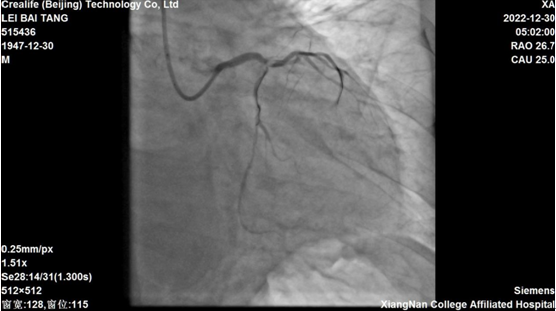

医院为老人完善心电图等检查,诊断为“急性心梗”,立即开通胸痛中心绿色通道,直接将患者送入导管室实施了急诊冠脉造影手术。“当时老人下左冠状动脉所发出两支大血管在造影时完全没有显影,意味着左主干完全闭塞,病情十分危急,随时有心脏骤停风险。”主管医生李华峰说。

时间就是心肌,时间就是生命!心血管内二科团队立即行动,协作配合,根据手术策略,在最短的时间内为患者实施了冠状动脉内溶栓术及球囊扩张术,快速开通了闭塞的血管,影像显示前向血流恢复良好。就在家属稍稍感到松口气的时候,医务人员却仍旧不敢有一丝懈怠。李华峰医生说,“根据患者病情,术后恢复期一样至关重要,老人依然有随时出现心衰的可能。”医务人员始终守护在老人身边,密切关注着他的生命体征变化,情况果然如李华峰所料,当天晚上老人出现双侧大量胸腔积液的情况。早有准备的医务人员及时为他行双侧胸腔穿刺置管引流术,同时予以积极抗心衰治疗。一周后,老人的病情终于逐渐稳定。